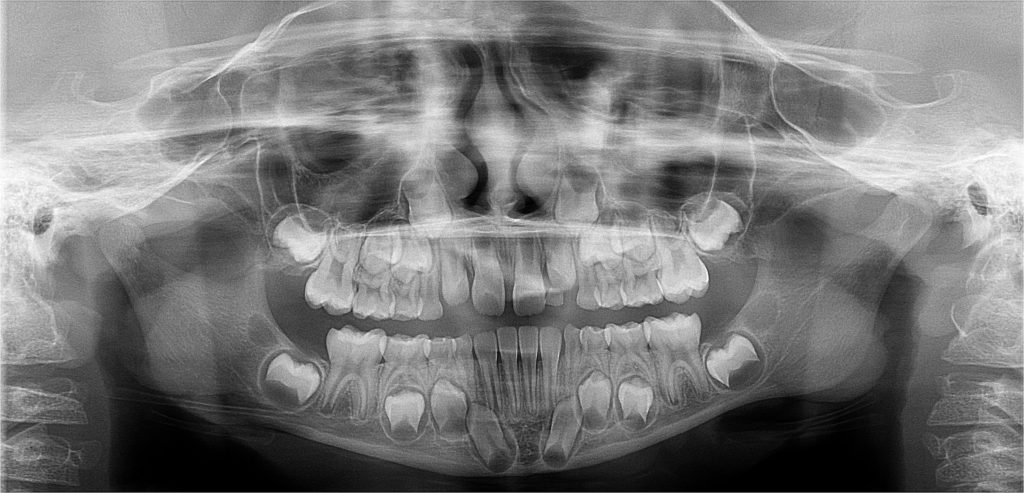

Contamos con el primer y único equipo de Rayos X digital de la ciudad.

Para diagnosticar y tratar las enfermedades orales de manera más eficaz y precisa a nuestros pacientes, y así otorgarles una atención integral y segura, evitándoles viajar cientos de kilómetros a otras ciudades para la toma de estos exámenes. Nuestro equipo de rayos x cuenta con todas las autorizaciones sanitarias para su instalación y desempeño.